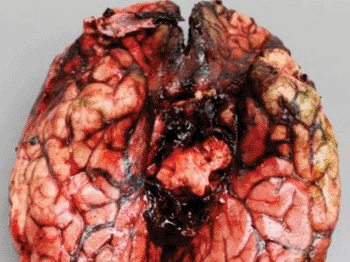

Image: Gross and histopathologic features of acute fatal Exserohilum meningitis. Hemorrhage around the base of the brain (Photo courtesy of the American Journal of Pathology).

Pathological Findings Reveal Details of the Fungal Outbreak from Contaminated Steroid Injections

Investigators have described the pathological findings they compiled during the extensive examination of tissue samples obtained from 40 patients infected with the fungus Exserohilum rostratum after having been injected with a contaminated steroid. More...